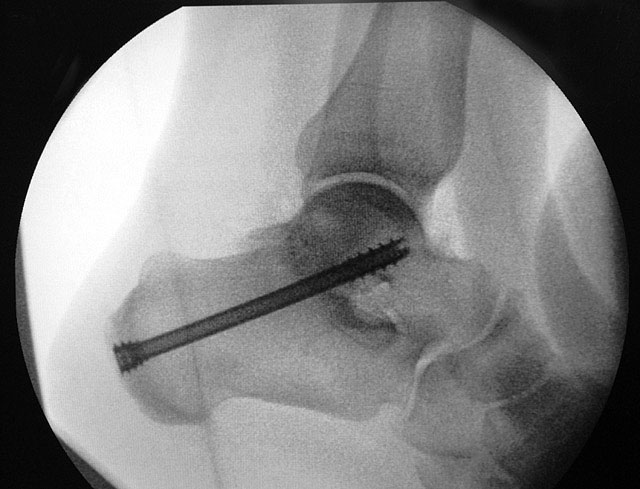

Je nach Operationsziel wird die Arthrodese des Subtalargelenks in verschiedenen Modifikationen durchgeführt. Ist der Rückfuß orthograd ausgerichtet, so erfolgt sie als in situ Fusion, d.h. ohne Korrektur Änderung der Rückfussachse. Liegt eine Rückfuß-Fehlstellung vor, kann diese durch ein additives oder substraktives knöcherndes Vorgehen korrigiert werden 12. Die Fixation der Arthrodese erfolgt üblicherweise mit (kanülierten) Schrauben die über den Tuber calcanei eingebracht werden 3. Eine zweite Schraube zur Sicherung der Rotationsstabilität wird optional über den Processus anterior calcanei im Talushals verankert 4. Der am häufigste verwendete Zugang zum unteren Sprunggelenk verläuft lateral subfibular, alternative Zugänge sind medial oder posterior möglich 56. Ist keine relevante Korrektur notwendig kann der Eingriff auch arthroskopisch durchgeführt werden 78.

Schraubenfehllage: Bei der intra-operative Röntgen-Kontrolle muss der Fuß exakt seitlich und das obere Sprunggelenk ap eingestellt werden, um die korrekte Lage der Schrauben beurteilen zu können.